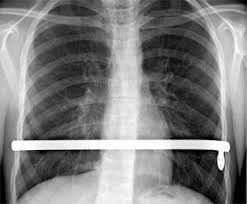

Greetings readers. I have spent the past few days to-and-froing from my son in the hospital undergoing a corrective surgery related to pectus carinatum, and full-family summer and researching the pros and cons of PDA (patron- or demand-driven acquisitions). I am very happy to say that after a nearly 5-hour surgery, in which we allowed “experts” to cut our son’s chest nipple to nipple, lay back the muscle, chip-scrape “excise” the cartilage out of his ribcage, crack his sternum, reshape him and insert a flexible metal bar…he is recovering smashingly, already walking about, playing card-games, and humorously retorting. This is the first “major” operation, injury, break, accident or otherwise that has occurred to my genetic offspring, and, although I’ve endured much trauma with the injuries and surgeries of my spouse, I was unsure what to anticipate going through in allowing invasive slicings and breakings to my precious son’s body.